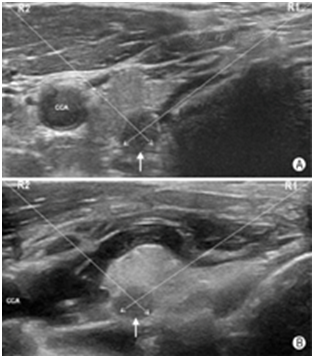

如图19所示,对于气管近旁尤其是2~5点钟位(以甲状腺横切面为参照表盘,于对侧腺体则应是7~10点钟位)的目标结节,穿刺操作宜选用由内向外穿刺法,同时操作者可使用液体隔离技术使目标病灶向外侧移位,增大端侧式穿刺进针的角度,以规避气管壁对穿刺针尖的阻碍,并改善穿刺针尖的显示清晰度。如图20所示,对于位于7~10点位(对侧腺体应是2~5点位)邻近颈总动脉的病灶,也宜选用由"内向外"穿刺法。同样,操作者也可采用液体隔离方法使得颈总动脉向外侧移位,增大目标病灶与颈总动脉之间的距离,避免误伤颈总动脉。

图19液体隔离法优化FNA穿刺路径 A:目标结节(箭头所示)紧邻甲状软骨,R1入路时穿刺针伤及甲状腺上动脉前包膜支及软骨的可能性较大,R2入路时有可能伤及颈总动脉;B:液体隔离后,目标结节(箭头所示)与甲状软骨和颈总动脉(CCA)的间距均增大,无论是经R1入路还是R2入路,穿刺针皆可安全规避甲状腺上动脉前包膜支、软骨及颈总动脉(R1:穿刺路径1,亦称"由内向外"穿刺路径,即由颈中线向外侧穿刺进针;R2:穿刺路径2,亦称"由外向内"穿刺路径,即由外侧经越胸锁乳突肌向经中线方向穿刺进针)